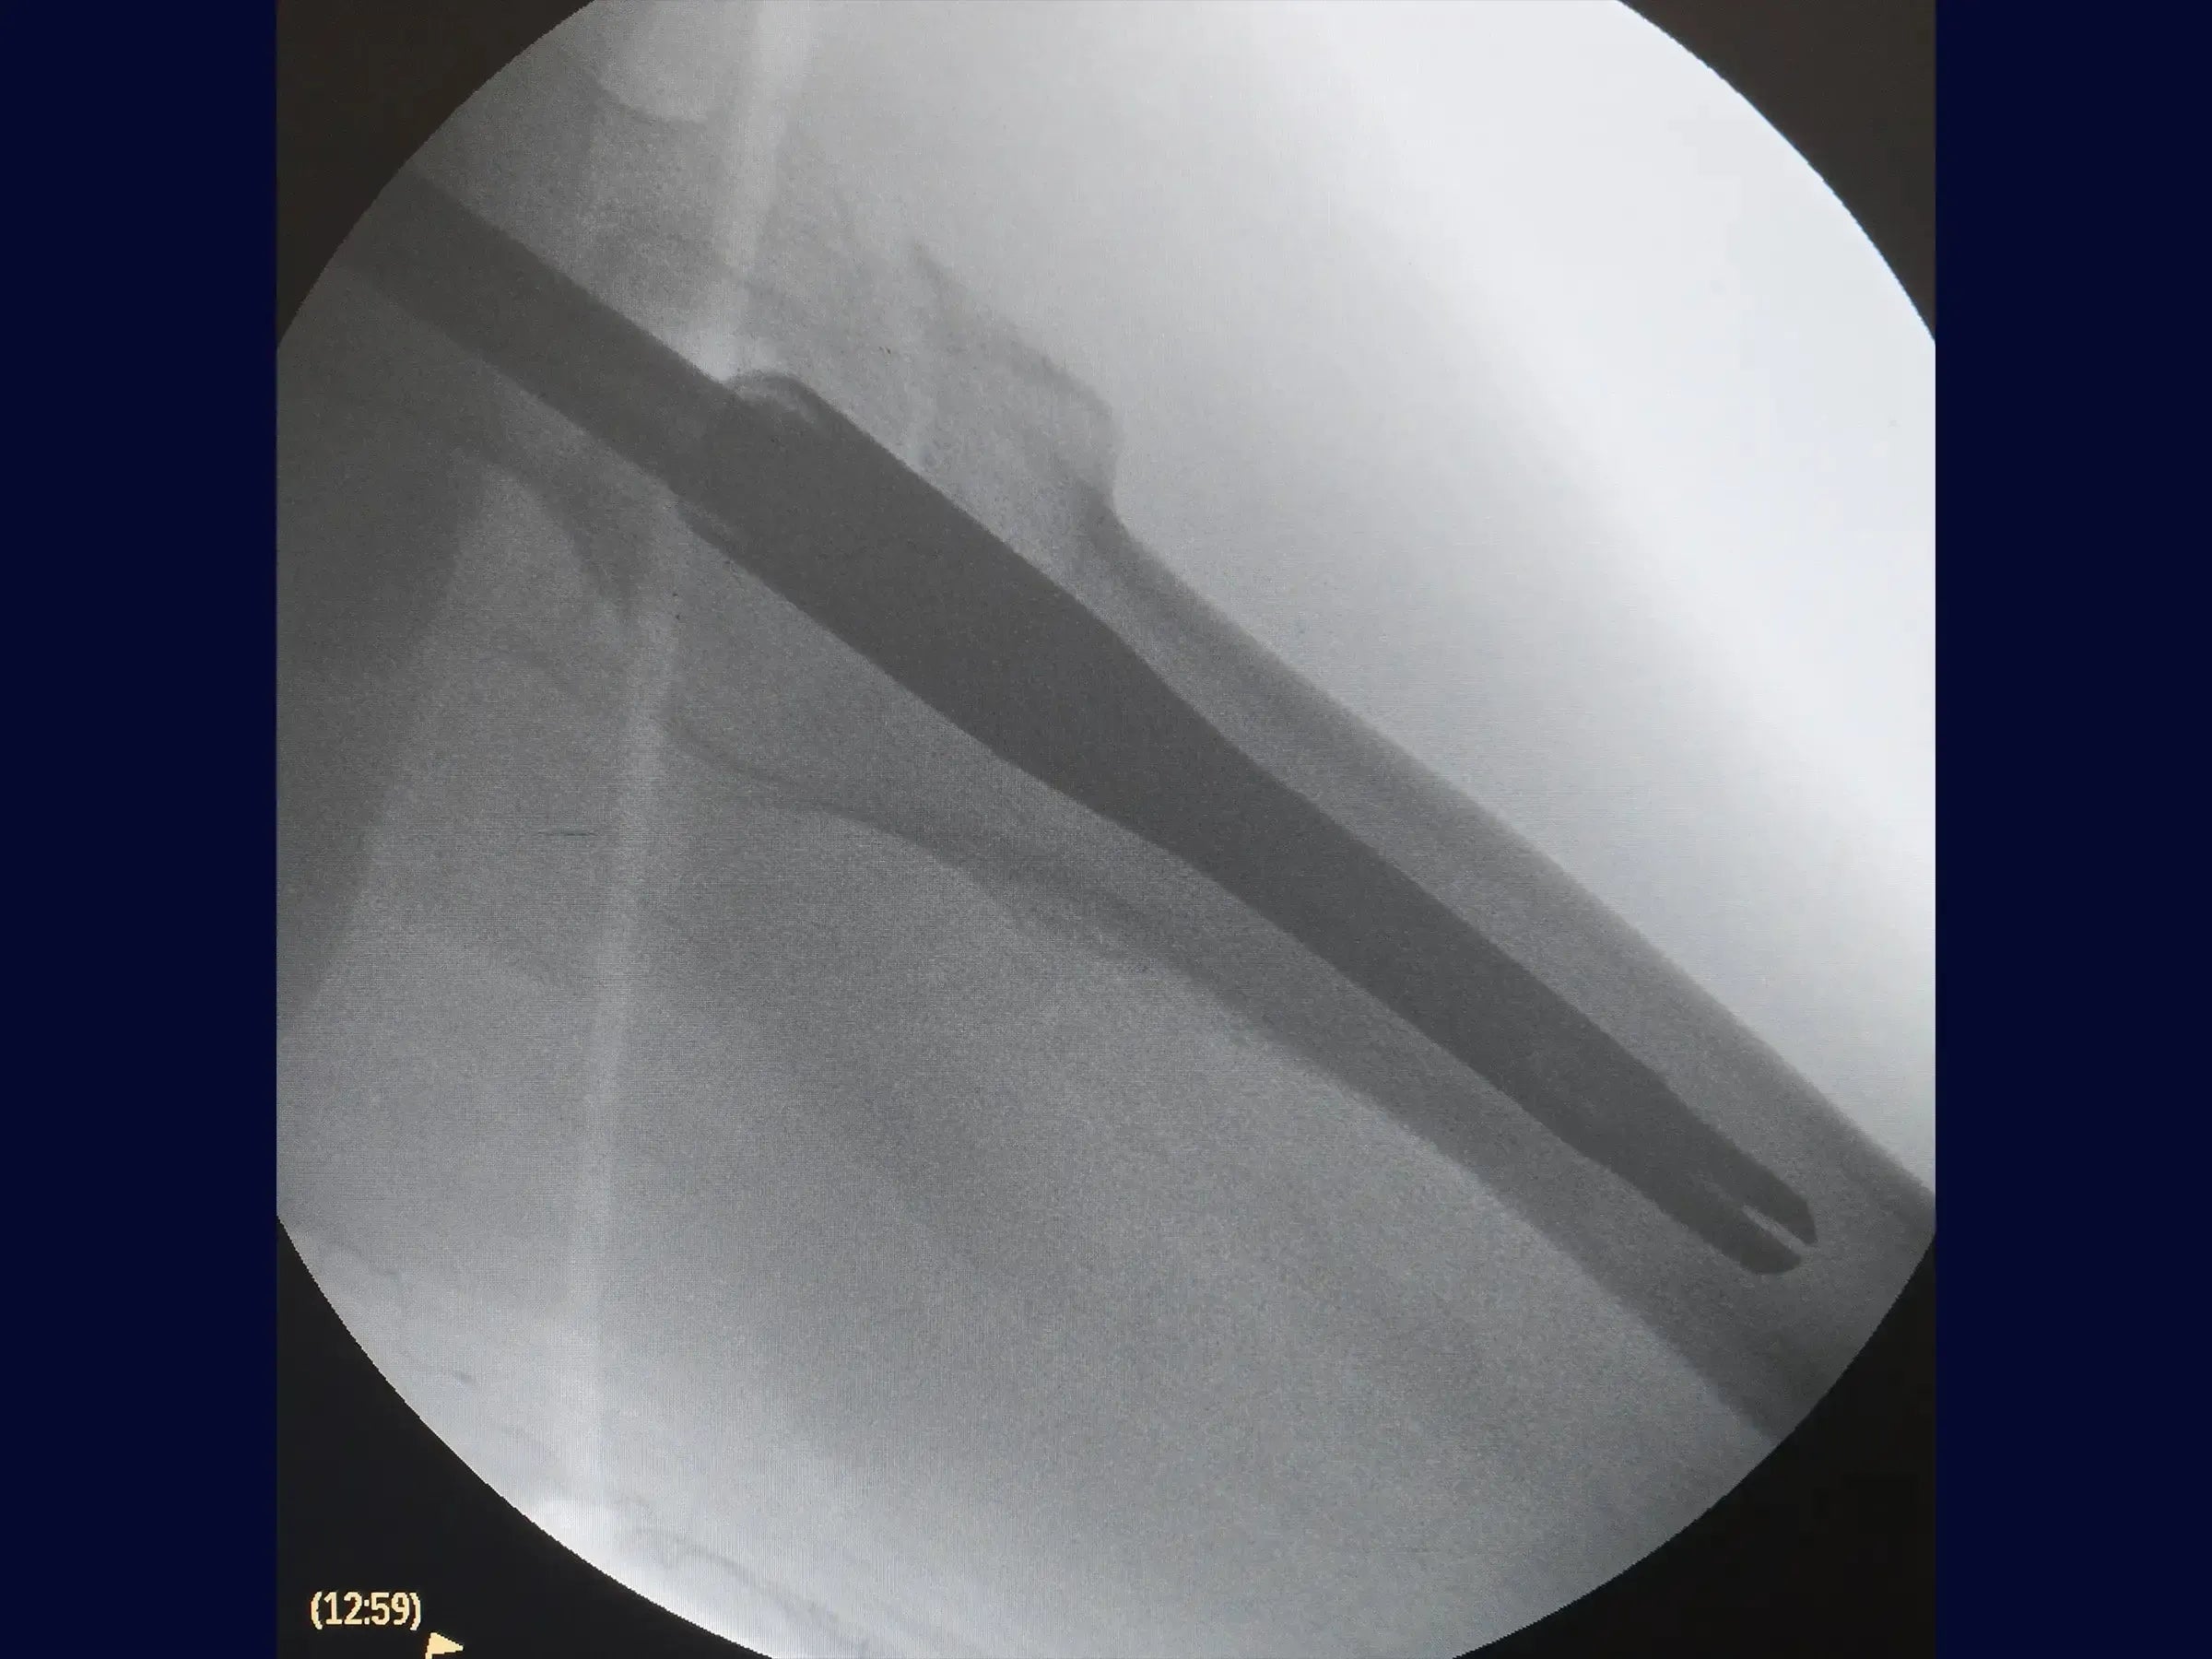

- Otimização Lateral e Haste: Para corrigir o posicionamento lateral do fio , use um guia de paralelismo que centraliza o fio no canal medular e colo femoral , evitando obliquidade do parafuso deslizante. Abra o canal medular com broca e protetor de partes moles, e introduza a haste intramedular curta.

- Inserção de Parafusos: Faça uma abertura minimamente invasiva lateral para o fio guia do parafuso deslizante, confirmando seu direcionamento para o centro da cabeça do fêmur em ambas as vistas. Meça e insira o parafuso deslizante, usando um segundo fio guia para evitar seu retorno. O bloqueio distal é guiado pelo introdutor da haste, com incisão de 1.5 cm. Certifique-se de que o parafuso deslizante permita pistonamento.